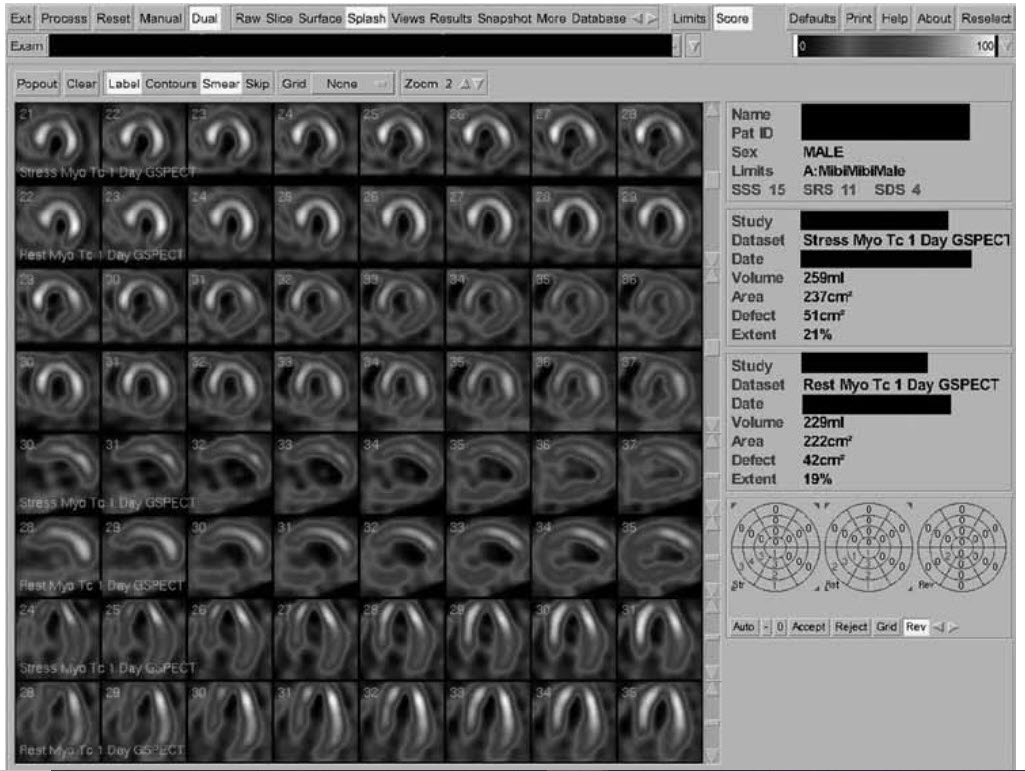

This 45-year-old patient’s coronary angiogram confirms a discrete mid-LMS lesion with a possible ostial RCA lesion following a recent admission with a minor troponin-positive episode of acute pulmonary oedema. Type 2 diabetes is the only risk factor. Echocardiography is difficult to assess because of obesity, but LV function is probably only mildy impaired. How would you proceed based on the MPS shown below?

A. Optimize medical therapy

B. Consider CABG

C. Consider PCI LMS

D. Refer for LVAD/transplant

E. Refer for FFR or IVUS